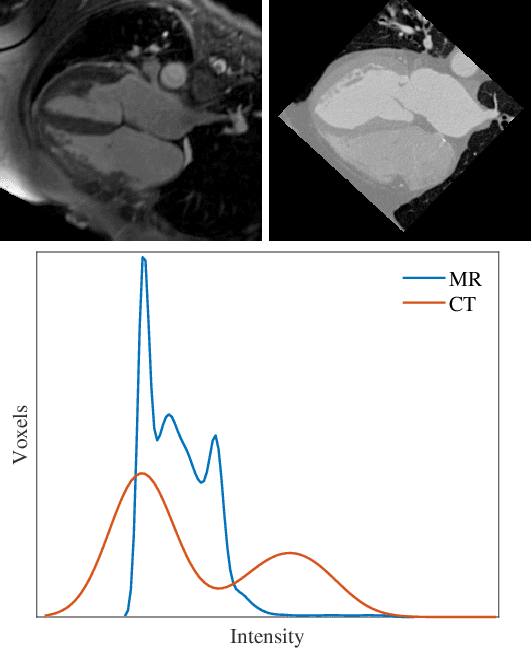

Abstract:Disentangled representation is a powerful technique to tackle domain shift problem in medical image analysis in unsupervised domain adaptation setting.However, previous methods only focus on exacting domain-invariant feature and ignore whether exacted feature is meaningful for downstream tasks.We propose a novel framework, called semantic-guided disentangled representation (SGDR), an effective method to exact semantically meaningful feature for segmentation task to improve performance of cross modality medical image segmentation in unsupervised domain adaptation setting.To exact the meaningful domain-invariant features of different modality, we introduce a content discriminator to force the content representation to be embedded to the same space and a feature discriminator to exact the meaningful representation.We also use pixel-level annotations to guide the encoder to learn features that are meaningful for segmentation task.We validated our method on two public datasets and experiment results show that our approach outperforms the state of the art methods on two evaluation metrics by a significant margin.